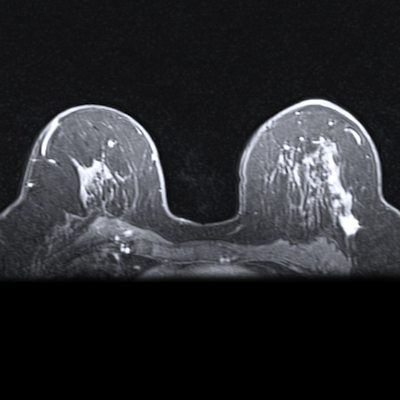

In her talk, Sabrina Walter, MD, from University Medical Centre Mannheim in Germany presented her team’s results showing how breast MRI shows more invasive breast cancers in these women, as well as how it may reduce underdiagnosis of both invasive and noninvasive cancers.

Walter highlighted MRI’s high sensitivity, specificity, negative predictive value, and cost-effectiveness in screening high-risk patients. She and colleagues studied how supplemental MRI adds to total breast cancers found in women with dense breasts after the women received a negative screening mammogram.

The study included data collected from 200 women with breast densities categorized as ACR C or D, indicating heterogeneously and extremely dense breasts, respectively.

Image-guided biopsy revealed four cancers, three of which were deemed invasive in women presenting with category C breast density. The other one cancer case was a non-calcifying ductal carcinoma in situ (DCIS) in a woman with category D breast density. This resulted in a cancer detection rate of 20 per 1,000, a positive predictive value (PPV) of recall of 50%, and a PPV of biopsy of 62.5%.